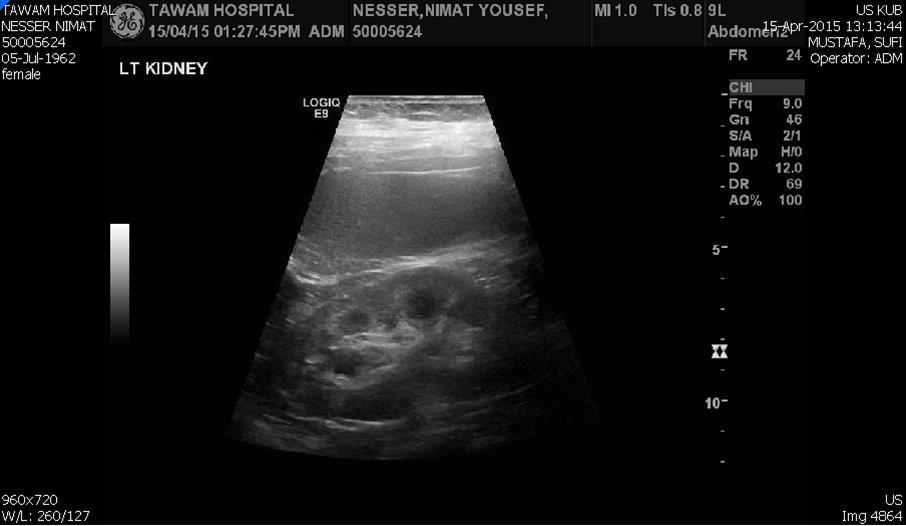

Blood tests on April 14th showed: Na = 131, K = 5.1, Urea = 6.9, S. Creatinine = 96, and eGFR = 61ml/min. Urine analysis and cultures confirmed E. coli urosepsis, blood cultures were negative. Renal US revealed echogenic kidneys, mild bilateral hydronephrosis of about 12 mm with normal ureters and urinary bladder (Figure 1 and Figure 2). Treatment with oral antibiotics resulted in improvement of temperature and dysuria. On April 20th patient seen by endocrinology and nephrology because of persistent back pain, dapagliflozin was discontinued and followed by resolution of symptoms in few days. Patient had two kidney ultrasounds in May and June, both indicated gradual resolution of bilateral hydronephrosis. Repeat CT of the abdomen on July 7th revealed complete resolution of hydronephrosis (Figure 3). Most recent eGFR is 72 ml/min.

Figure 2.Left kidney hydronephrosis